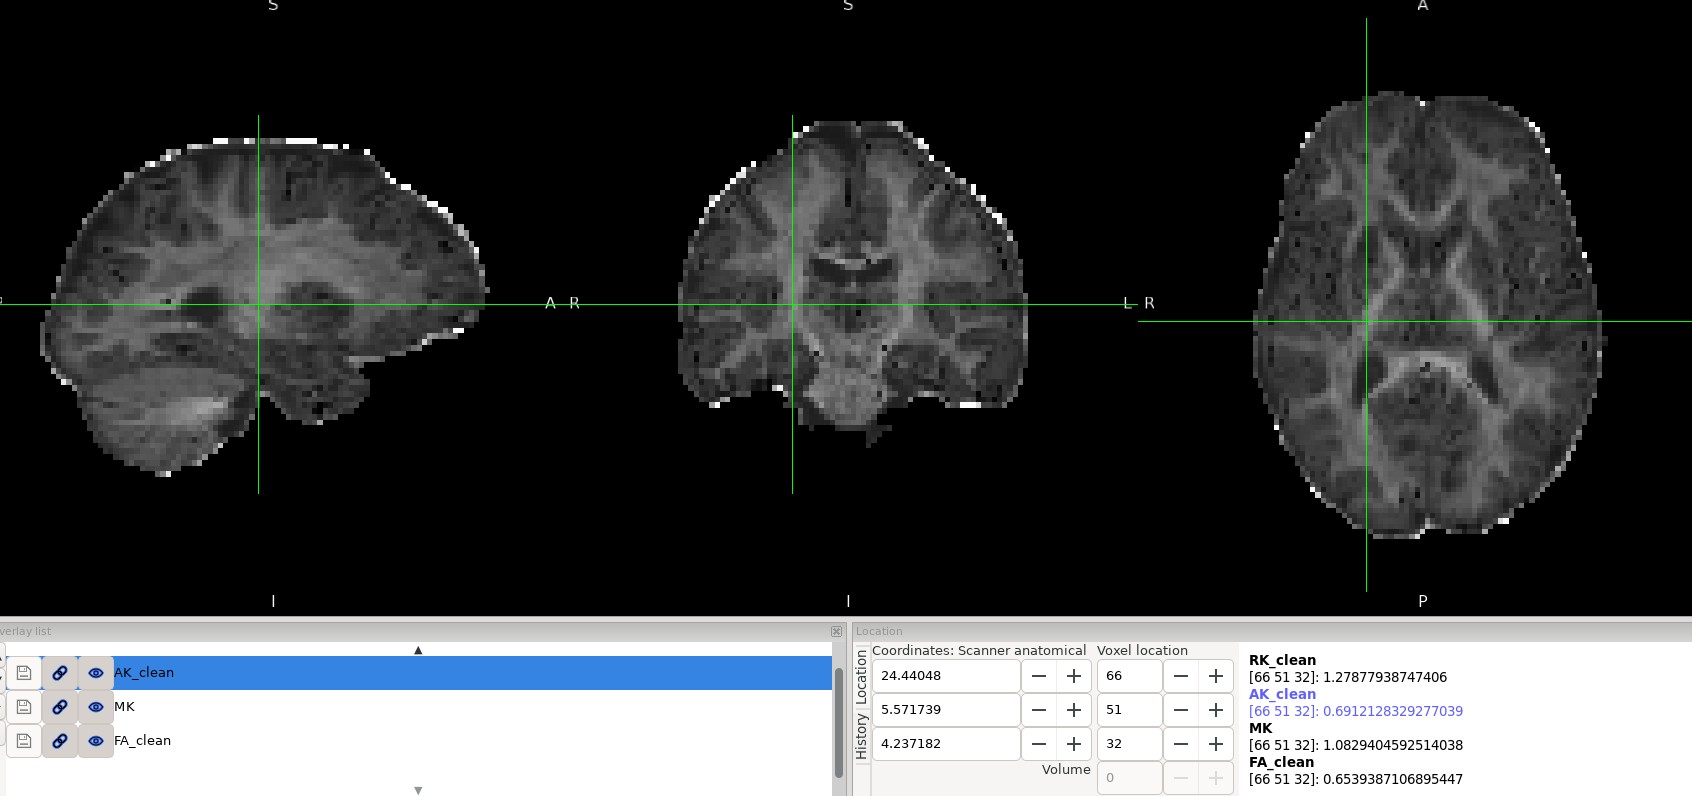

Overall, the results look reasonable; however, as shown in the image, there are a few black voxels, corresponding to values that are lower than expected, in the splenium and genu of the corpus callosum.